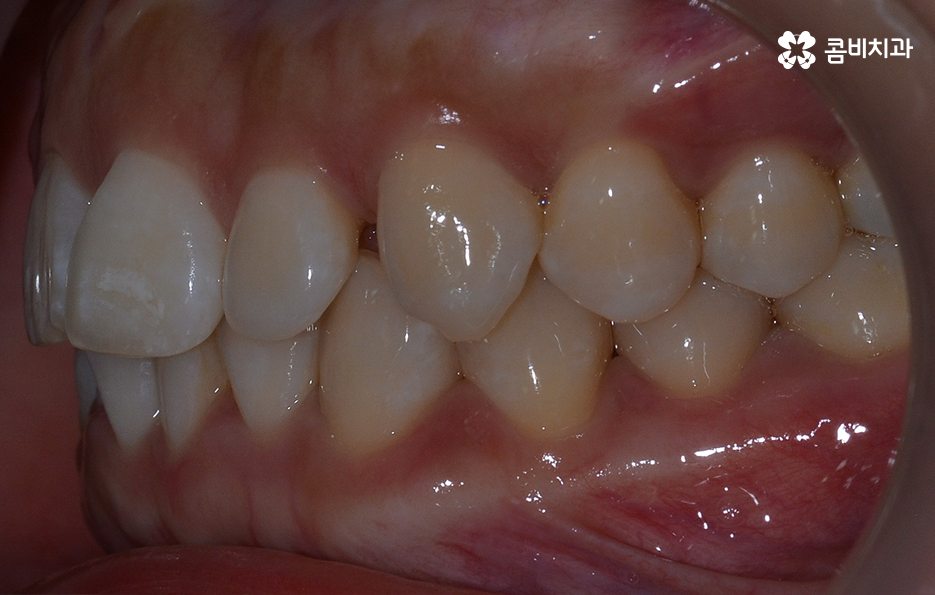

교정 치료는 크게 발치와 비발치치아교정으로 나뉠 수 있는데 비발치치아교정의 경우에는 아무래도 치아가 움직이는 양도 적고 그에 따라 교정 기간도 짧은 편에 해당되고 있어요.

교정을 하게 되면 아무래도 치아와 잇몸이 함께 움직이기 때문에 어느정도는 잇몸이 약해질 가능성이 있는데 비발치치아교정의 경우에는 치아의 이동이 큰 편은 아니기 때문에 발치교정에 비해서는 잇몸이 약해지는 정도 및 확률이 줄어들 수 있어요

반면에 발치교정의 경우에는 최소 1년 6개월 ~ 2년 이상의 교정 기간이 소요되며 치아가 빠진 공간에 나머지 치아들이 메우면서 치아의 이동이 비발치치아교정에 비해 많기 때문에 그에 따라 치아는 물론 치조골의 이동도 감안해야 하므로 치료 기간도 더 오래 걸리고 잇몸도 좀더 약해질 수 있는 확률이 발치교정에 비해서는 높은 편으로 볼 수 있는데요.

이러한 비교는 기본적으로 치아 이동의 정도 차이로 인해 치아 뿐 아니라 치조골의 이동이 큰 만큼 확률적으로 잇몸이 약해질 가능성이 상대적으로 크다는 의미로 볼 수 있어요.